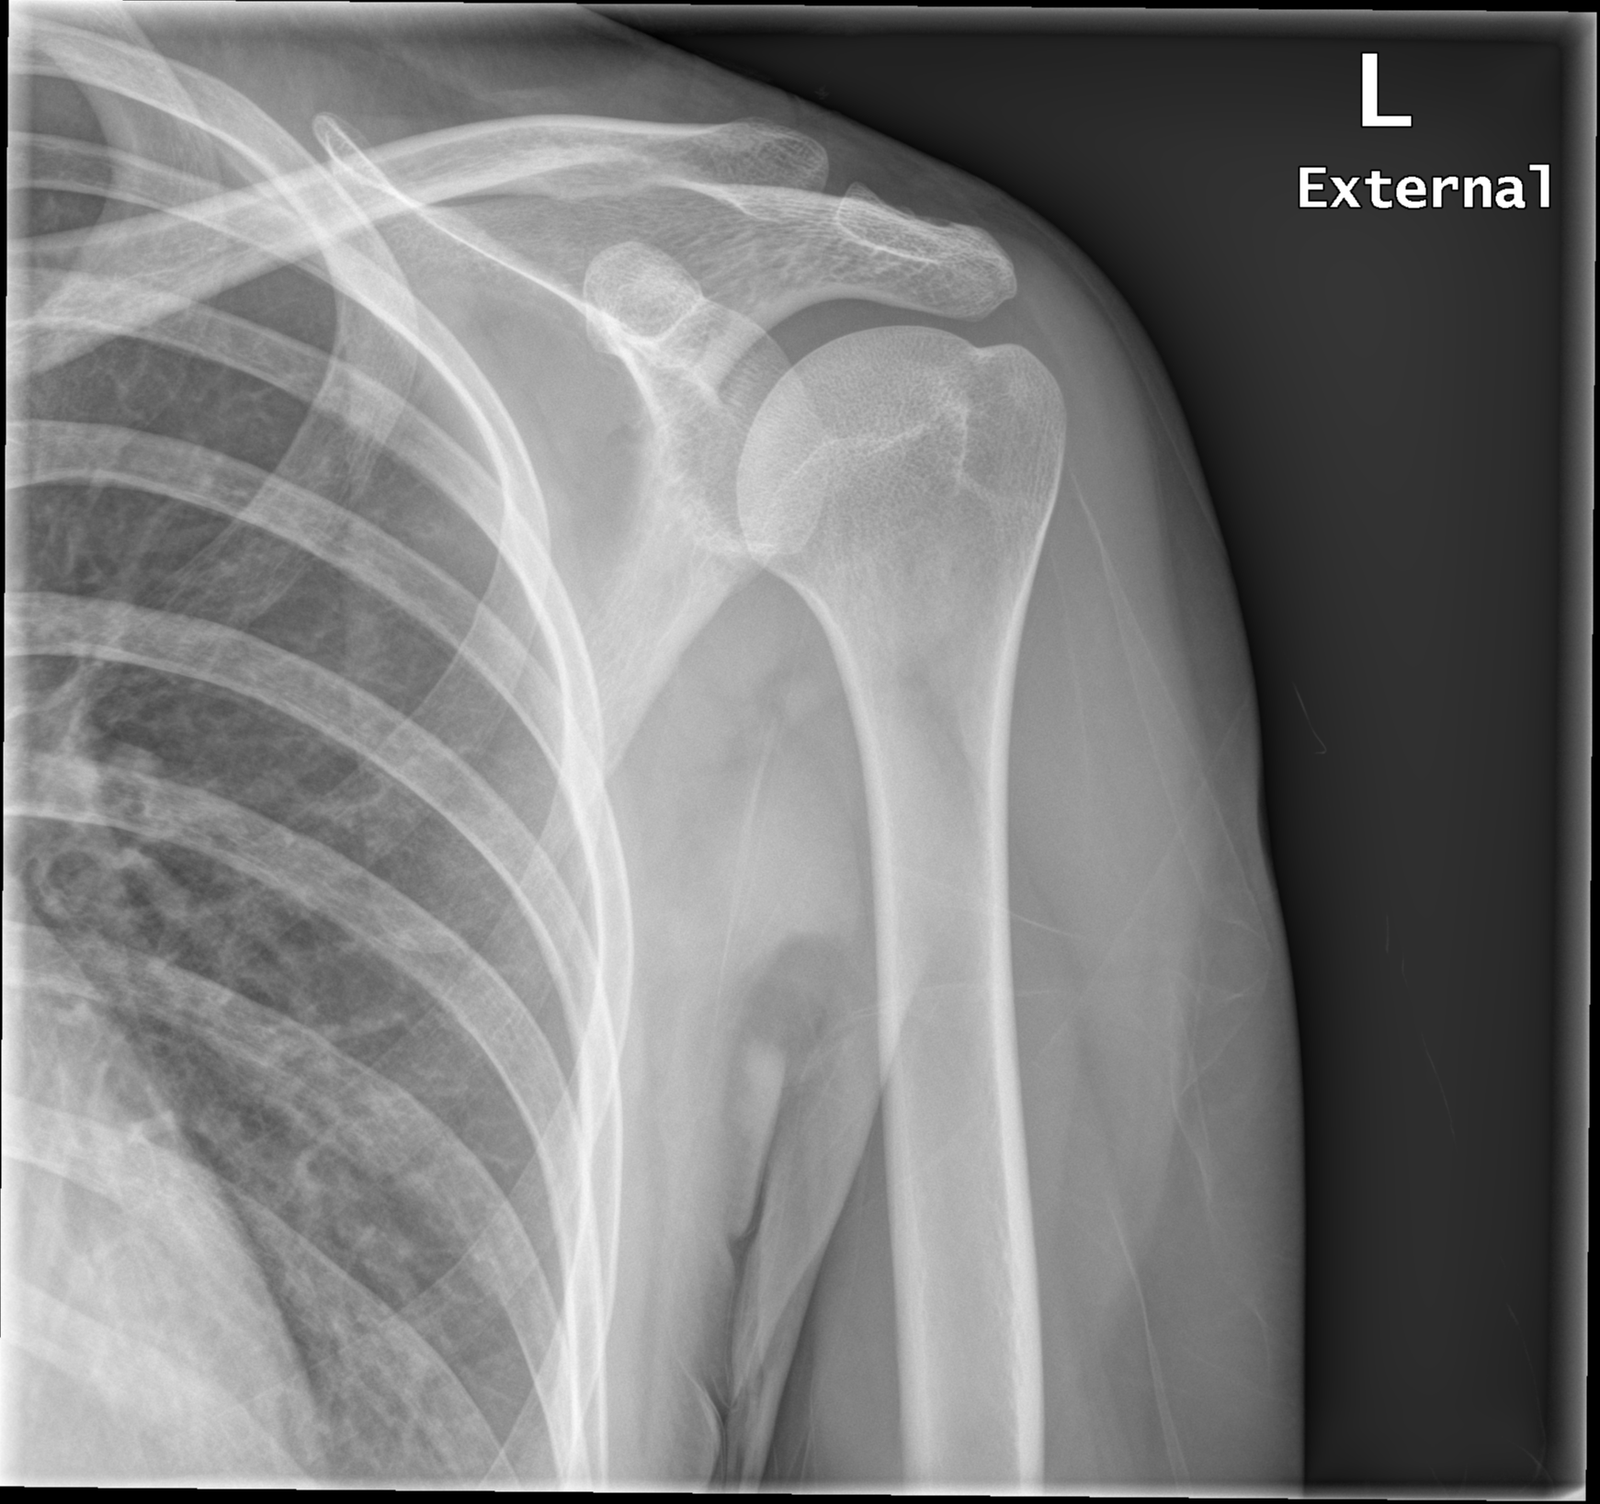

Learn how to perform the Empty Can Shoulder Test to accurately assess supraspinatus weakness and rotator cuff pathology. This guide explains the step-by-step clinical examination technique, helping practitioners identify shoulder impingement syndrome and potential tendon tears. Discover how this essential orthopedic assessment helps diagnose common shoulder injuries and guides effective treatment plans for improved patient mobility and pain relief.

Read full article: Empty Can Shoulder Test